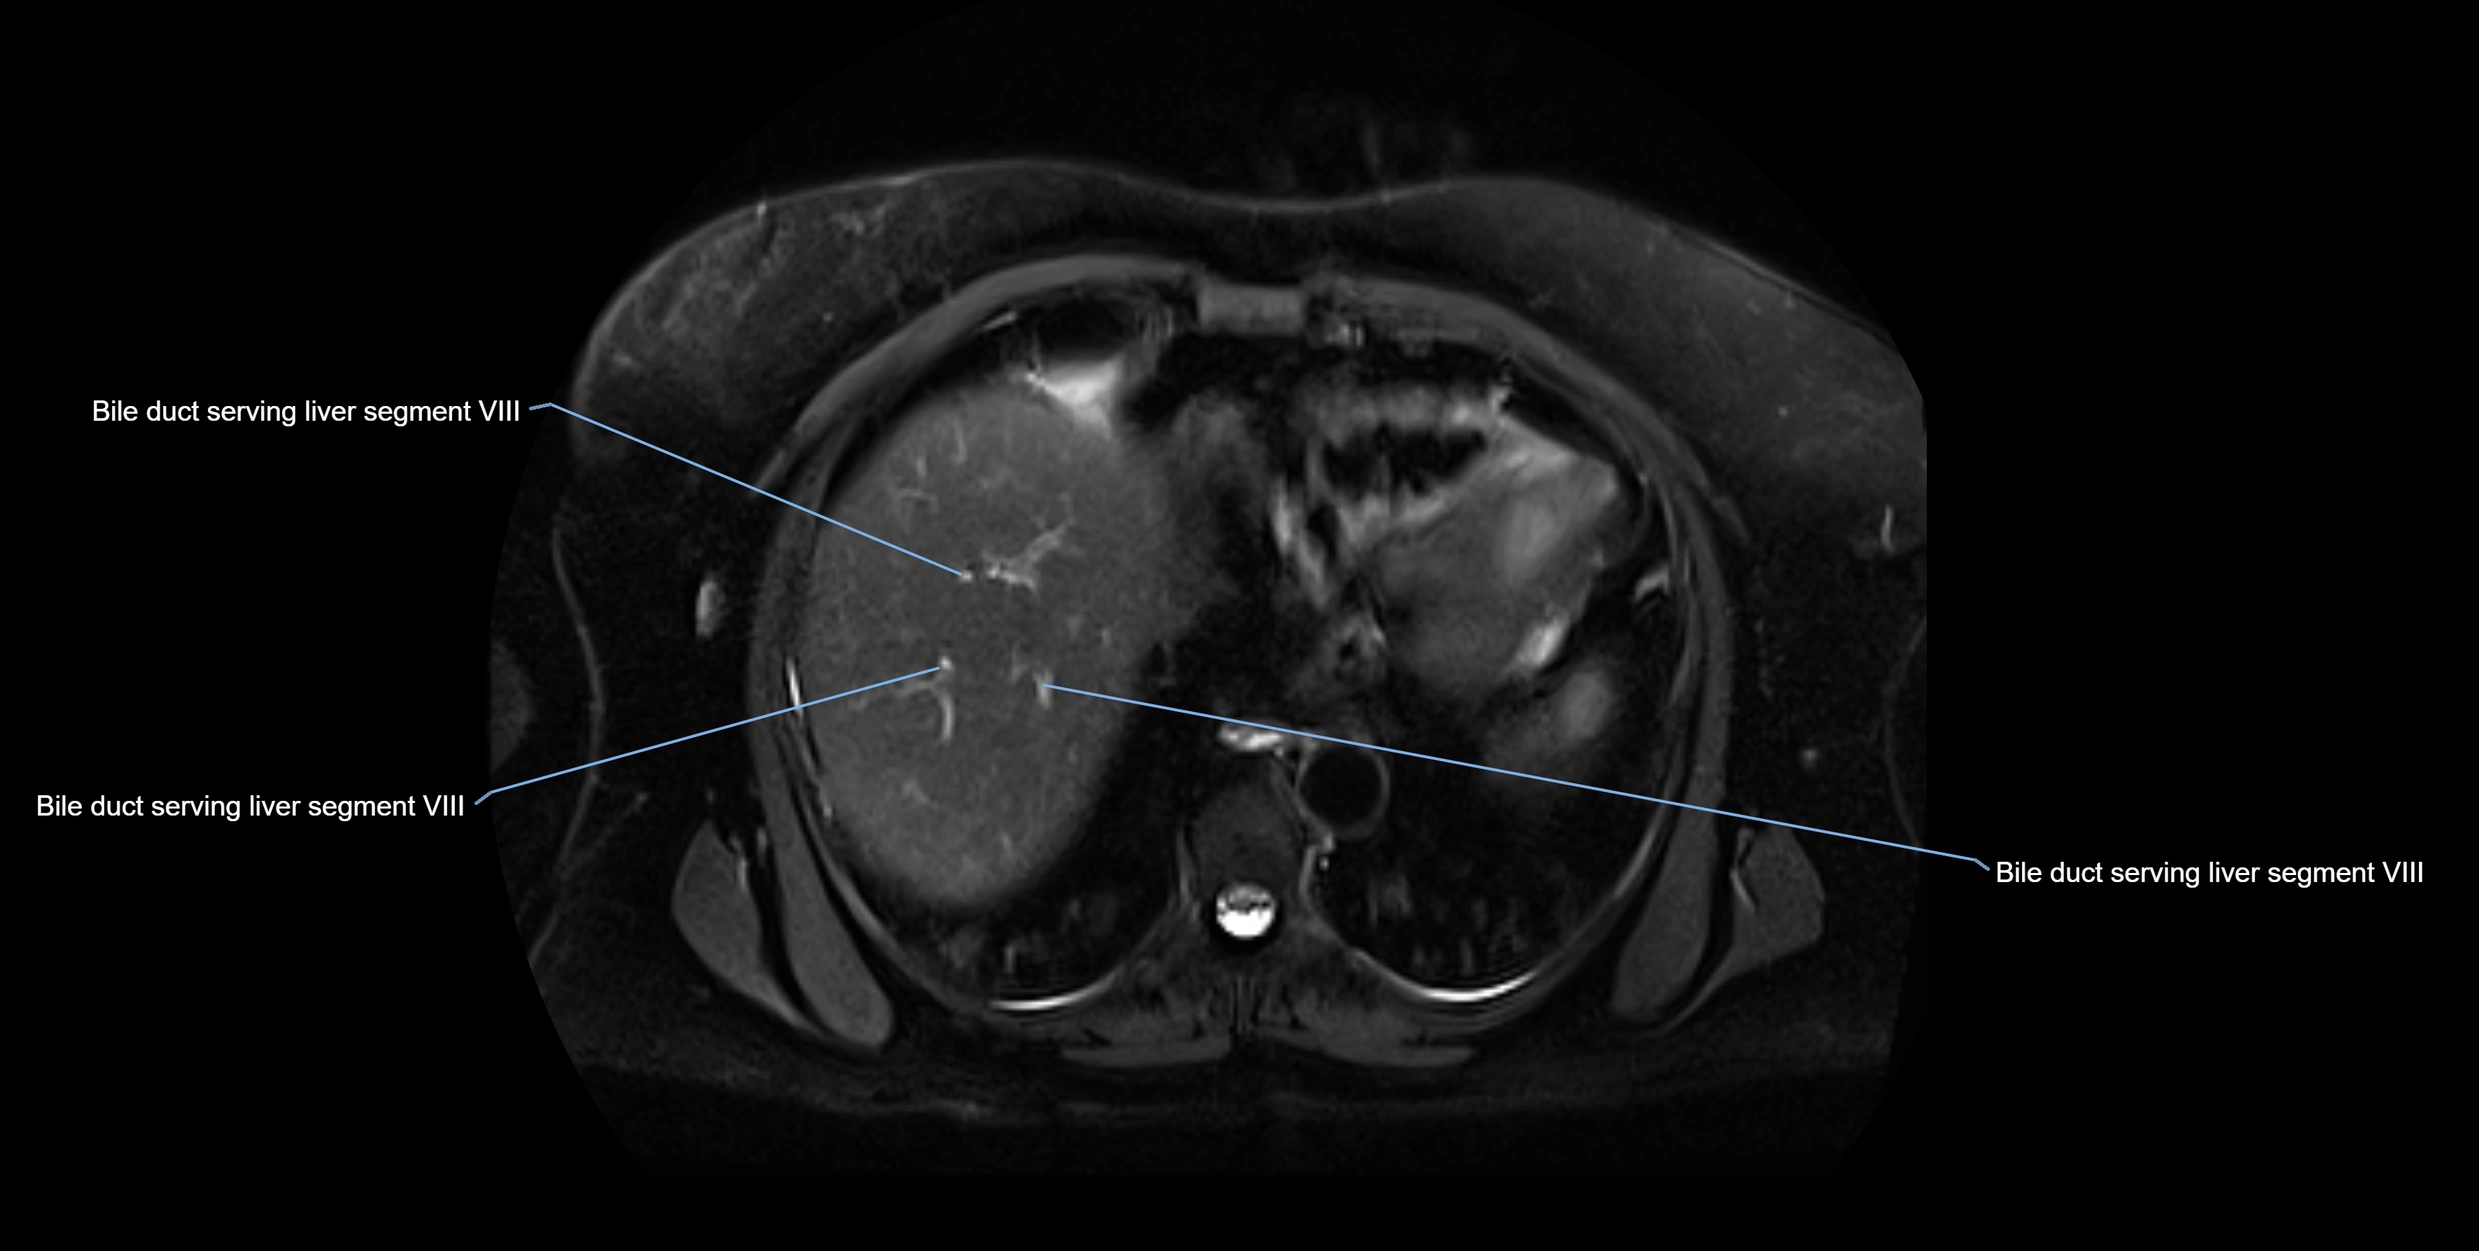

MRI image

image